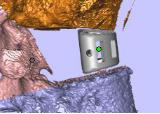

假体置于病例模型中

截骨导板放置位置

将脊柱模型添加支撑,把模型及导板3D打印出实物。

术前指导模型及截骨导板